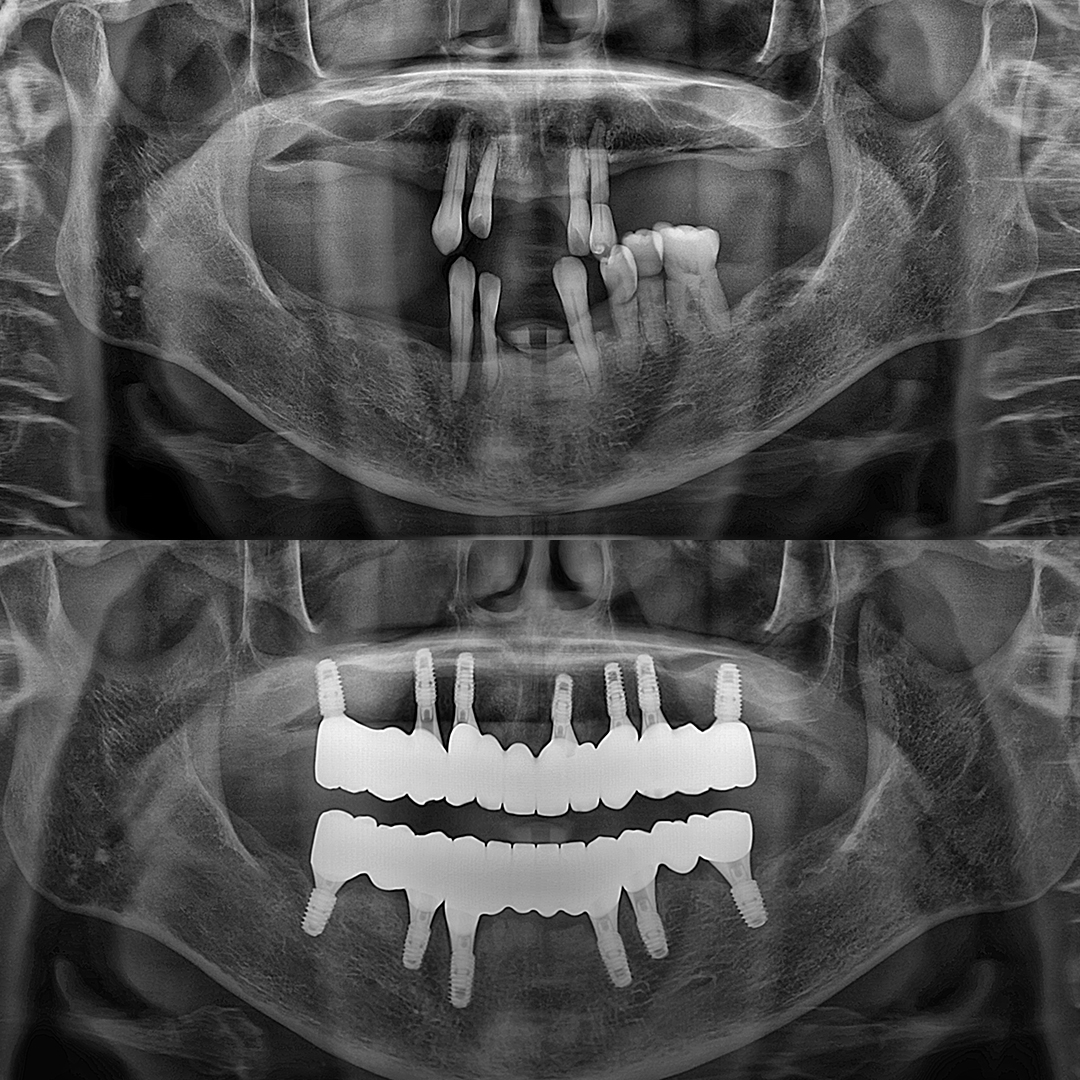

디지털 기술로 더 정확하고 확실하게

디지털(스마트) 임플란트

디지털 스캐닝 기술을 이용해 정교한 3D 모델을 만들고

임플란트의 정확한 위치에 식립하여 높은 정밀도와 맞춤형 치료를 제공합니다.

평균 악당 30분의 빠른 식립시간, 치료 케이스 다수 보유

전체 임플란트

상·하악 전체 치아를 대체하는 임플란트로 최소한의 식립을 통해

자연치아와 비슷한 기능을 수행할 수 있도록 합니다.